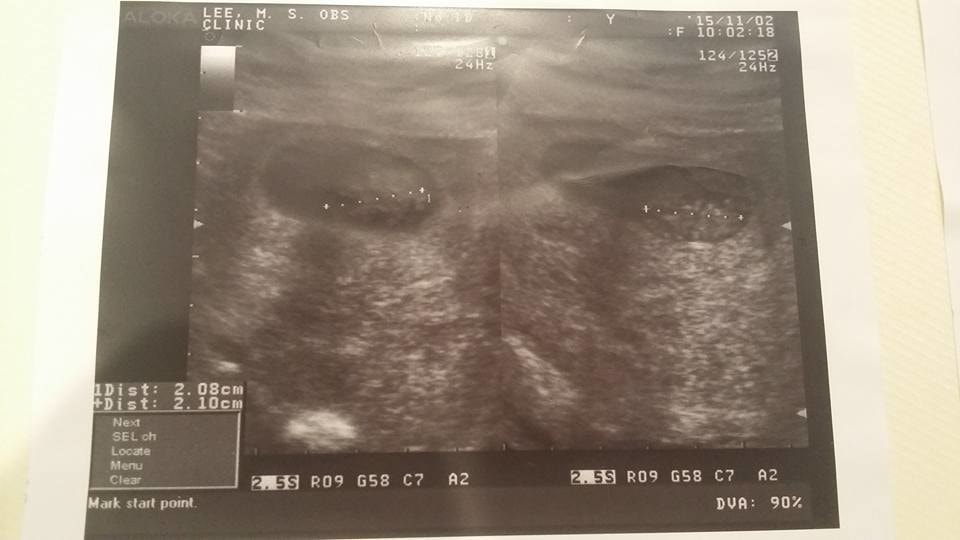

20151102-48KG8W產檢今天回診看寶寶,距離上次才四天的時間而已,三個寶寶的小手,小腳都已經長出來囉!真的是超級可愛的。而且今天同卵雙胞其中一個非常頑皮的動來動去,讓護士要找手跟腳還稍微壓了一下肚子,才讓寶寶不要再揮揮手跟腳。三個寶寶很健康,從頭,心臟,…